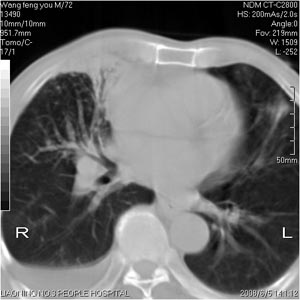

患者:男 72岁 右肩痛半年,近日来咳血,就诊.

右肺中心型肺癌并上叶不张,右侧胸腔积液,做镜检吧.

典型右中心型肺癌并右肺上叶不张,左肺转移,右胸腔积液。

考虑:右肺上叶中心型肺癌伴肺不张、肋骨转移、肩胛骨转移、右侧胸腔积液。

1.考虑:右肺上叶中央型肺癌并右肺上叶不张及右侧多发肋骨、上纵隔淋巴结及左肺转移。

2.右侧胸腔积液。